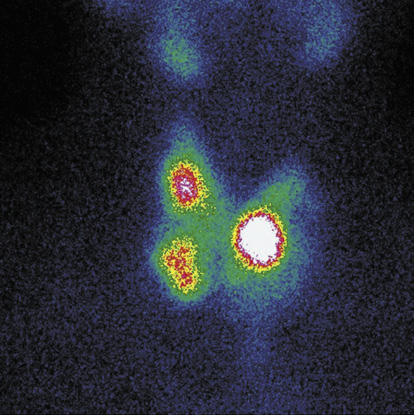

6. Fig. 6. Multinodular toxic goiter (functional autonomy of the left thyroid lobe, combined with hyperfunctioning nodular formations of the right lobe). | |

| Subject | ||

| Type | Other | |

View

(89KB)

|

Indexing metadata ▾ | |